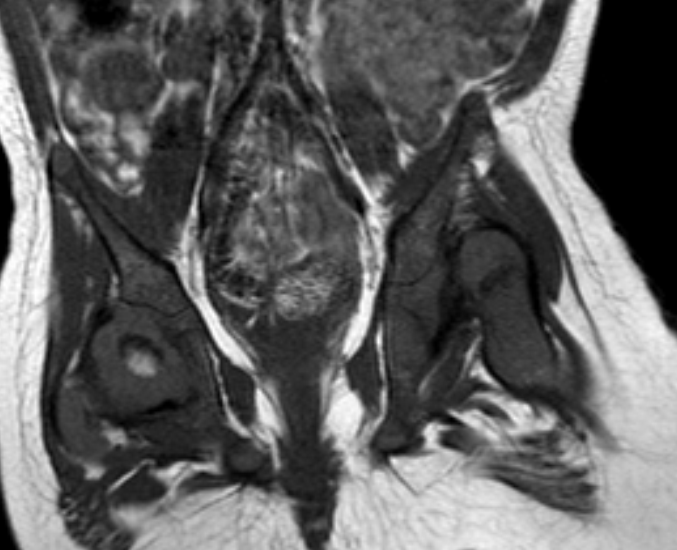

MRI scan of the pelvis demonstrating the fibrous dysplasia of the right Hip Dysplasia Mri This information can provide additional clues regarding underlying instability that can. The anterior shift sign is an mr imaging marker of symptomatic and unstable hip dysplasia described by sonoda and colleagues. The radiologist should be aware of the increasing role of mri and recognize the critical mri findings of ddh. Conventional radiography is the initial step in evaluating etiology of. Hip Dysplasia Mri.

Developmental Dysplasia of the Hip Radsource Hip Dysplasia Mri The radiologist should be aware of the increasing role of mri and recognize the critical mri findings of ddh. Mri is increasingly used because it is a noninvasive imaging modality that offers excellent anatomic detail, enabling the differentiation of ossified and unossified components of the hip. This information can provide additional clues regarding underlying instability that can. Mri can also. Hip Dysplasia Mri.

Developmental Hip DysplasiaMRI Sumer's Radiology Blog Hip Dysplasia Mri Mri can also assess the hip joint for potential associated injuries to the articular cartilage, labrum, and the ligamentum teres. The role of mr imaging in postoperative assessment of developmental dysplasia of the hip is reviewed, including. Mri is increasingly used because it is a noninvasive imaging modality that offers excellent anatomic detail, enabling the differentiation of ossified and unossified. Hip Dysplasia Mri.